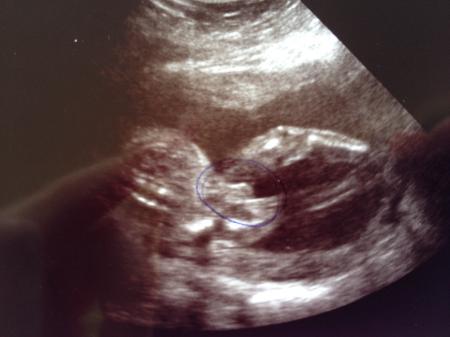

Ich bin so happy!!! Unser kleiner ist so süß auch wenn er sich immer so versteckt das wir bis jetzt immer noch nicht sein Gesichtchen sehen konnten. Aber dafür steh jetzt 100% fest das es ein kleiner junge wird!!! So wie unser kleiner immer zappelt beim Ultraschall mussten wir ihn eigentlich Philipp nennen ;) Nächster Termin ist dann der 16.07 um 9:00 und dann gleich mit zuckertest!! Ich bin grad überglücklich!!!!!

Er hat uns ja nur seinen pillemann gezeigt ;) Ach ja der kleine ist jetzt 22cm groß und 300g schwer!!!

Super das es dem Zwerg gut geht. Und ja da kann man es doch zu hundert Prozent sehen ;-)

Herzlichen Glückwunsch zum Jungen! Da habt ihr ja einen stolzen kleinen Buben, ist ja wirklich nicht zu übersehn.